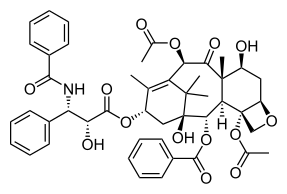

Advances in this field have led to the introduction of development of some therapies targeted at spindle assembly defects. Older treatments such as vinca alkaloids and taxanes target microtubules that accompany mitotic spindle formation via disruption of microtubule dynamics which engage the SAC arresting the cell and eventually leading to its death.[77] Taxol and Docetaxel, which can induce mitotic catastrophe, both are still used in the treatment of breast cancer, ovarian cancer and other types of epithelial cancer.[78] However, these treatments are often characterized by high rates of side effects and drug resistance.